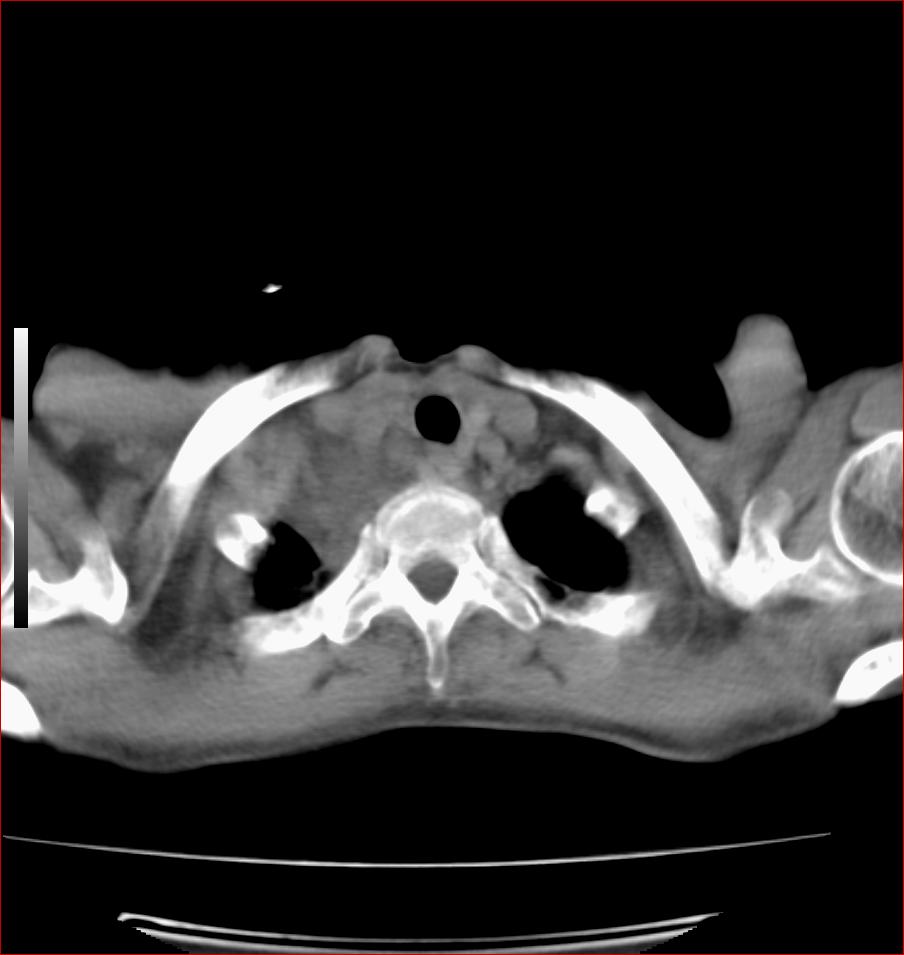

标题: CT17110:F56Y,纵隔囊肿;胸腺?淋巴?请各位老师看看 [打印本页]

女性患者 56 咽痛伴声嘶10+天入院。

右上纵隔囊性占位性病变;考虑支气管囊肿可能。

病变紧贴气管右壁,两者相互压迫,考虑支气管囊肿!

见相互挤压征,考虑气管囊肿,建议ct增强扫描